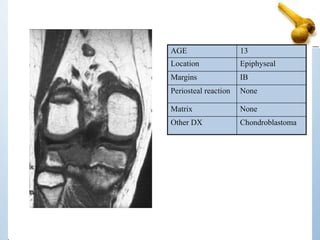

13 Y/O WITH KNEE PAIN

AGE 13

Location Epiphyseal

Margins IB

Periosteal reaction None

Matrix None

Other DX Chondroblastoma